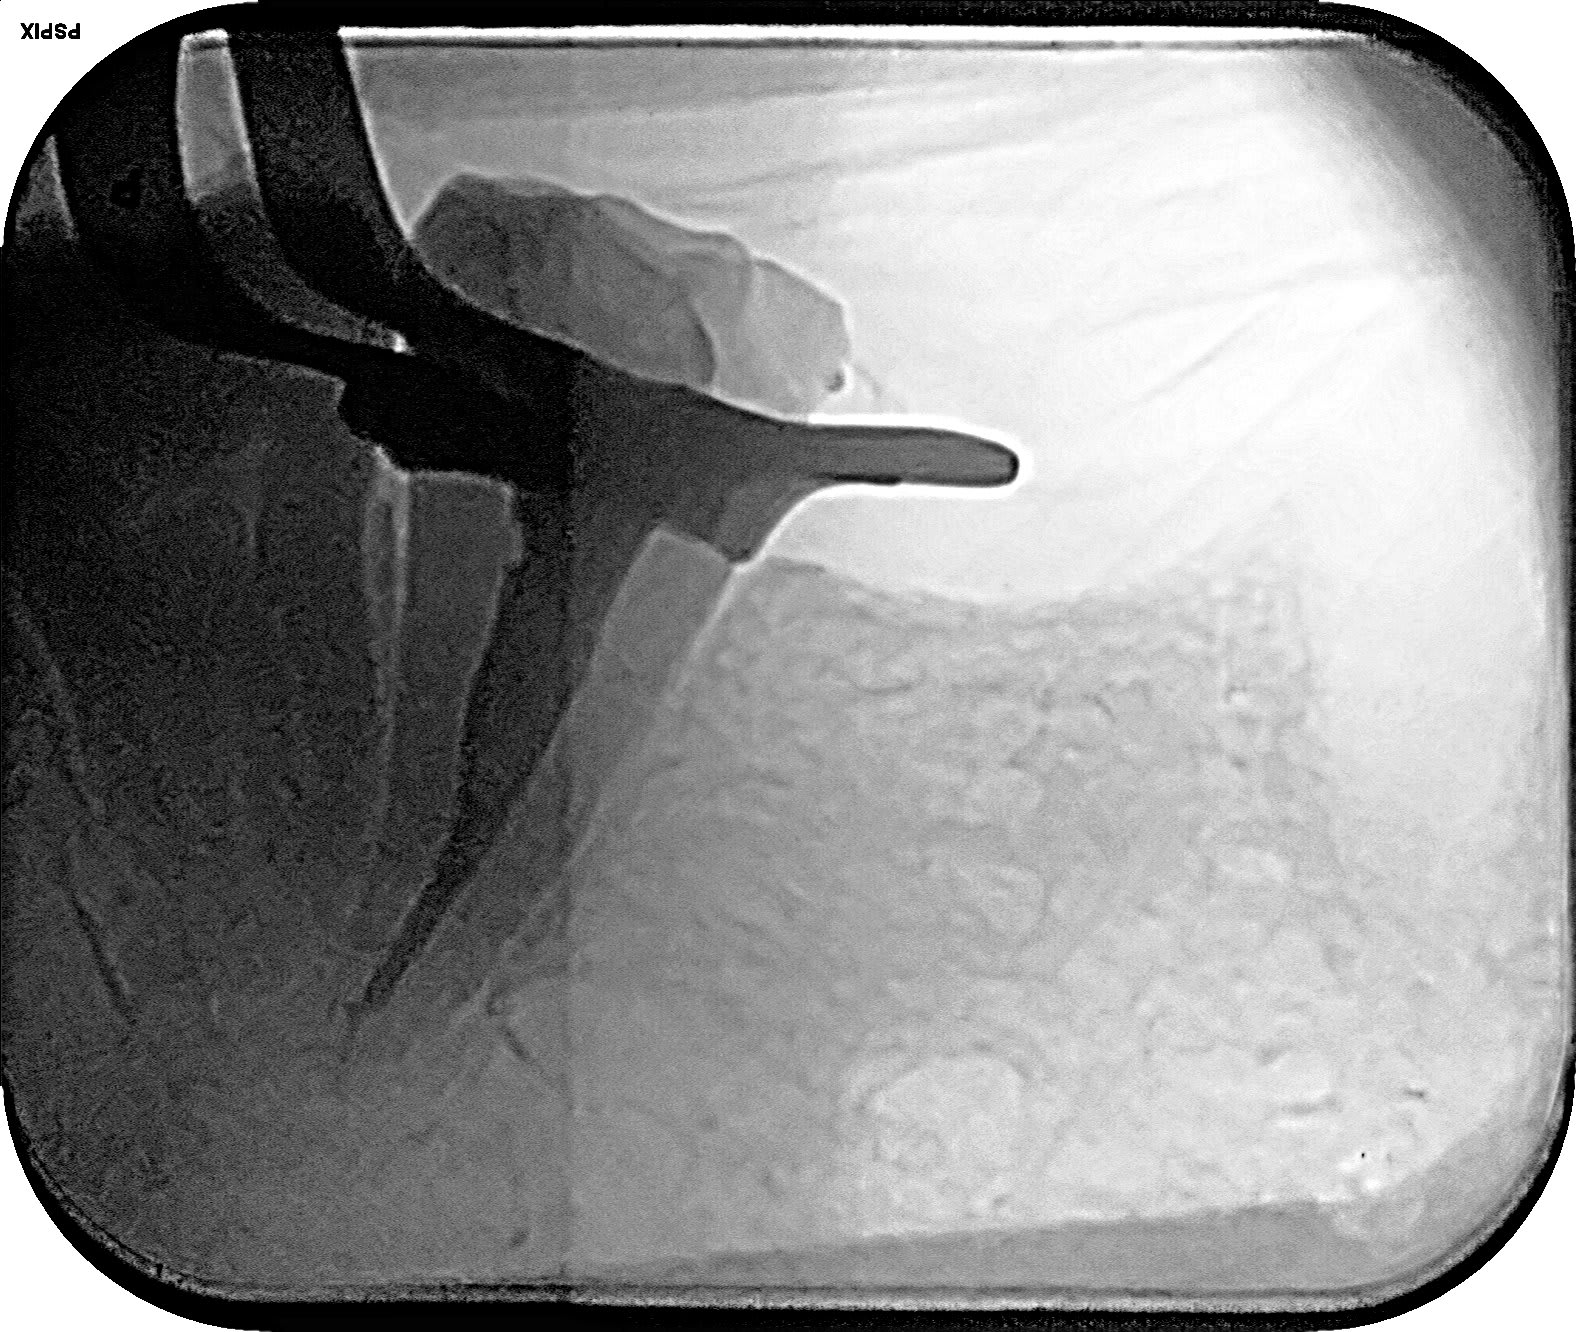

tronculaire... qualité radio pas top:-(

Injection, le temps de sortir le matos des sachets, c'était pris... merkiki ? le tendon profond 😉

Endo 37 bis isphmz - Eugenol

Endo 37 reyf7u - Eugenol